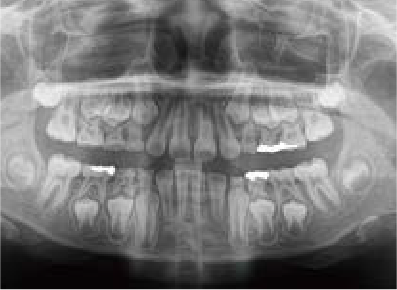

Jさん (矯正開始時:8歳)

Before

After

歯がガタガタに並んでいて、前歯の真ん中の位置が少し左にずれていました。

奥歯が生えるためのスペースが足りず、永久歯が生えて来られない状況が確認できました。

また、飲み込むとき下くちびるに力が入ってしまうクセが見られ、お顔全体の成長が遅れている様子が確認できました。

治療を終えて

歯がきれいに生えるためのスペースをしっかり確保することができ、歯並びを乱していたお口のクセも改善されたため、奥歯が生えるスペースを確保することができました。

しっかり噛めるかみ合わせを作ることが、将来の健康につながるので「よく噛む」練習も続けてもらっています。

主訴・治療内容 歯がガタガタになってきたことに悩み、無料相談に来院されました。

治療期間 3年

費用 462,000円(税込)